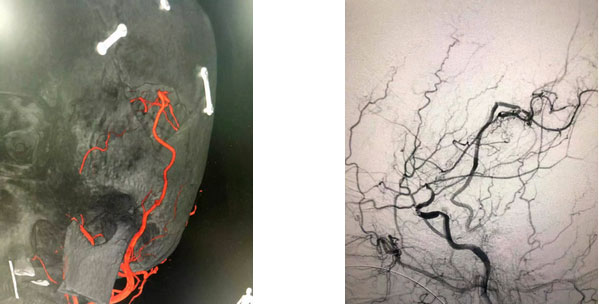

▲ 吻合口完美縫合

張琪博士在劉春醫(yī)生和周林華醫(yī)生協(xié)助下,在顯微鏡下將顱外顳淺動(dòng)脈游離后引入顱內(nèi),與大腦中動(dòng)脈分支行端側(cè)吻合。由于吻合血管直徑僅1mm左右,手術(shù)中在顯微鏡下使用僅有頭發(fā)絲直徑1/3的縫合線(10-0線)將吻合口縫合12針,才最終保證吻合口通暢并且無漏血。同時(shí),進(jìn)行硬腦膜翻轉(zhuǎn)術(shù)。隨后在復(fù)合手術(shù)室環(huán)境下,進(jìn)行腦血管造影,顯示搭橋血管血流通暢,頸動(dòng)脈血流通暢,頸外動(dòng)脈造影見顳淺動(dòng)脈血流向受體動(dòng)脈兩端供血,搭橋手術(shù)成功,整個(gè)手術(shù)過程持續(xù)了5個(gè)多小時(shí)。

▲ 術(shù)后影像

術(shù)后,經(jīng)過評(píng)估,患者腦血流得到明顯改善,患者目前恢復(fù)良好,已經(jīng)由術(shù)前淺昏迷狀態(tài)慢慢清醒,并可以下床活動(dòng)。